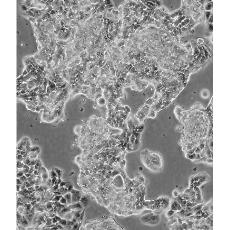

ZR-75-1 [ZR751]

產(chǎn)品名稱 ZR-75-1 [ZR751]

中文名稱 人乳腺癌細胞

組織來源 浸潤性導(dǎo)管癌;腹水轉(zhuǎn)移;女性

生長特性 adherent

形態(tài)特征 epithelial

細胞描述 該細胞產(chǎn)生高水平的黏液素MUC-1 mRNA,低水平的MUC-2 mRNA,但不表達MUC-3基因;表達雌激素受體。